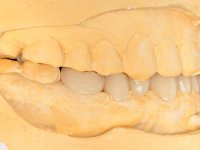

Avaliada a situação inicial em conjunto com o médico dentista, foi considerado prioritário alterar a forma dos dentes, subir 1.5mm a D.V.O. e descruzar a mordida do 1º Quadrante. Na confeção da ponte provisória superior de acrílico com reforço metálico foram já ensaiadas essas alterações. Optamos por um monobloco de 13 dentes com o intuito de manter a estabilidade posicional dos dentes re- preparados. Após remoção das coroas e pontes antigas foi feita a re-preparação dentária. A ponte provisória foi rebasada em boca, primeiro com acrílico auto-polimerizável e depois com resina composta. Após 4 semanas de integração da ponte provisória superior foi confecionada a ponte provisória inferior, corrigindo-se finalmente as discrepâncias existentes no plano oclusal. As impressões foram realizadas com a técnica de dupla mistura, com dupla mistura. Simultaneamente foram feitos os registos da relação inter-maxilar e da relação do maxilar superior com a base do crânio, utilizando o arco facial. Montados os modelos de trabalho em articulador semi-ajustável, foram confecionadas as peças próteticas, utilizando tecnologia CAD-CAM para a realização das infra-estruturas em zircónia. A colocação da cerâmica foi feita procurando que a forma dos dentes reproduzisse uma forma anatómica natural. A tonalidade foi condicionada pela vontade do paciente. Foi feita uma prova com a cerâmica em “biscuit” para verificação técnica e validação estética. Após aprovação pelo paciente o trabalho foi finalizado e colocado em boca.